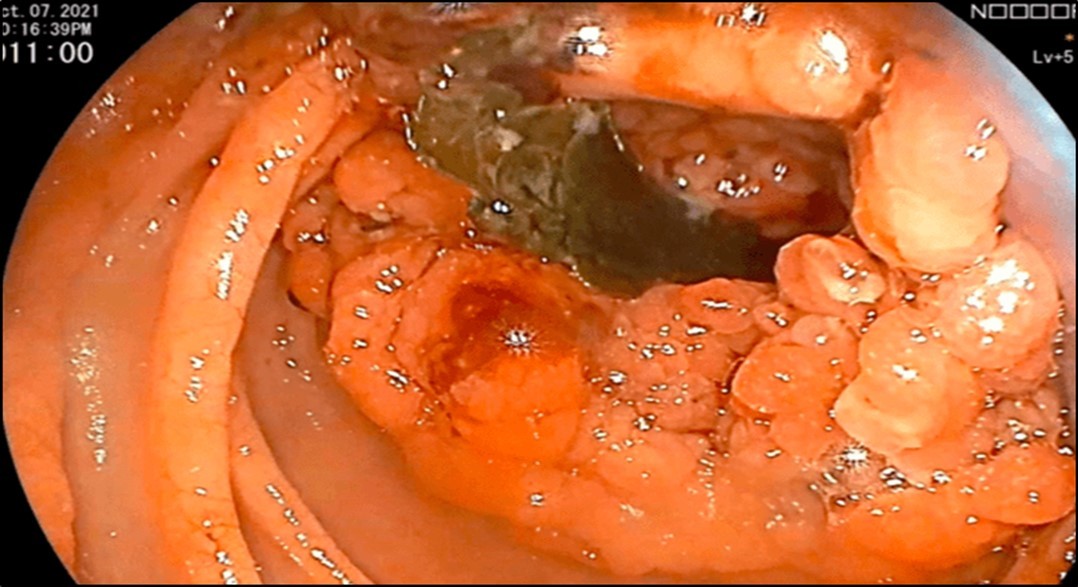

Esophagogastroduodenoscopy (EGD) revealed a fistulous opening in the third part of the duodenum and a bleeding vessel. (Figure 1) Bleeding was controlled with injection hemostasis and 3 hemoclips were deployed. The colonoscopy revealed a large obstructing, polypoid, ulcerating, and circumferential mass with areas of necrosis that was seen at the proximal transverse colon which precluded further advancement of the scope. Biopsy samples were sent for histopathology investigation and TB polymerase chain reaction (PCR) test.

Figure 1.EGD findings of a pathologic lumen and a bleeding vessel were seen at the third portion of the duodenum.